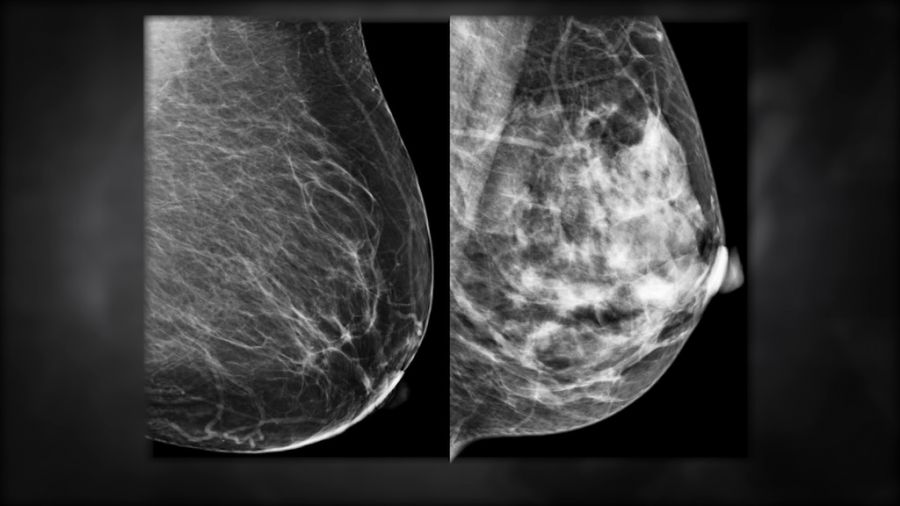

Se conmemora el Día de Concientización del Cáncer de Mama